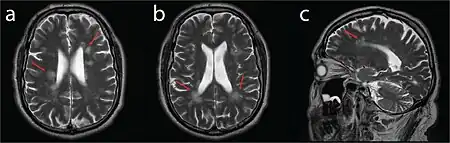

| MRI compatible with Dejerine-Sottas type spinal nerve enlargement | |

On medical imaging, the nerves of the extremities (and cranial nerves in some cases) appear enlarged due to hypertrophy of the connective interstitial tissue, giving the nerves a distinct "onion-bulb" appearance. Peripheral (and possibly cranial) nerve excitability and conduction speed are reduced.[1]